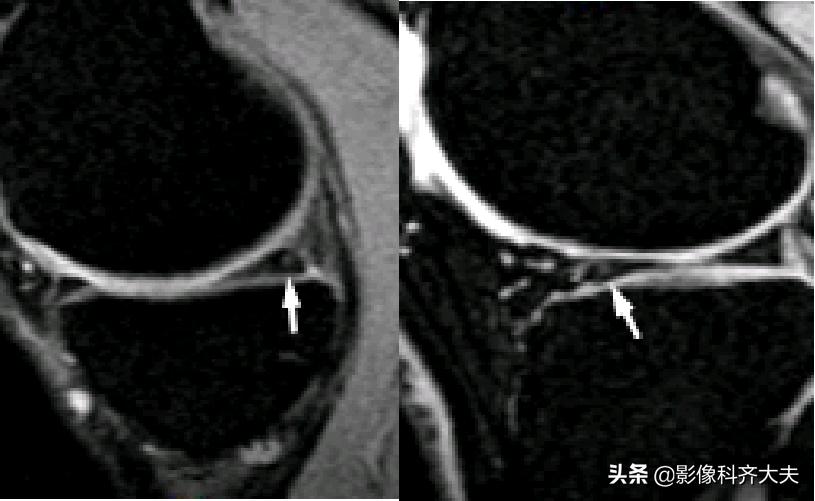

容易误诊为半月板损伤的正常解剖结构

膝横韧带: